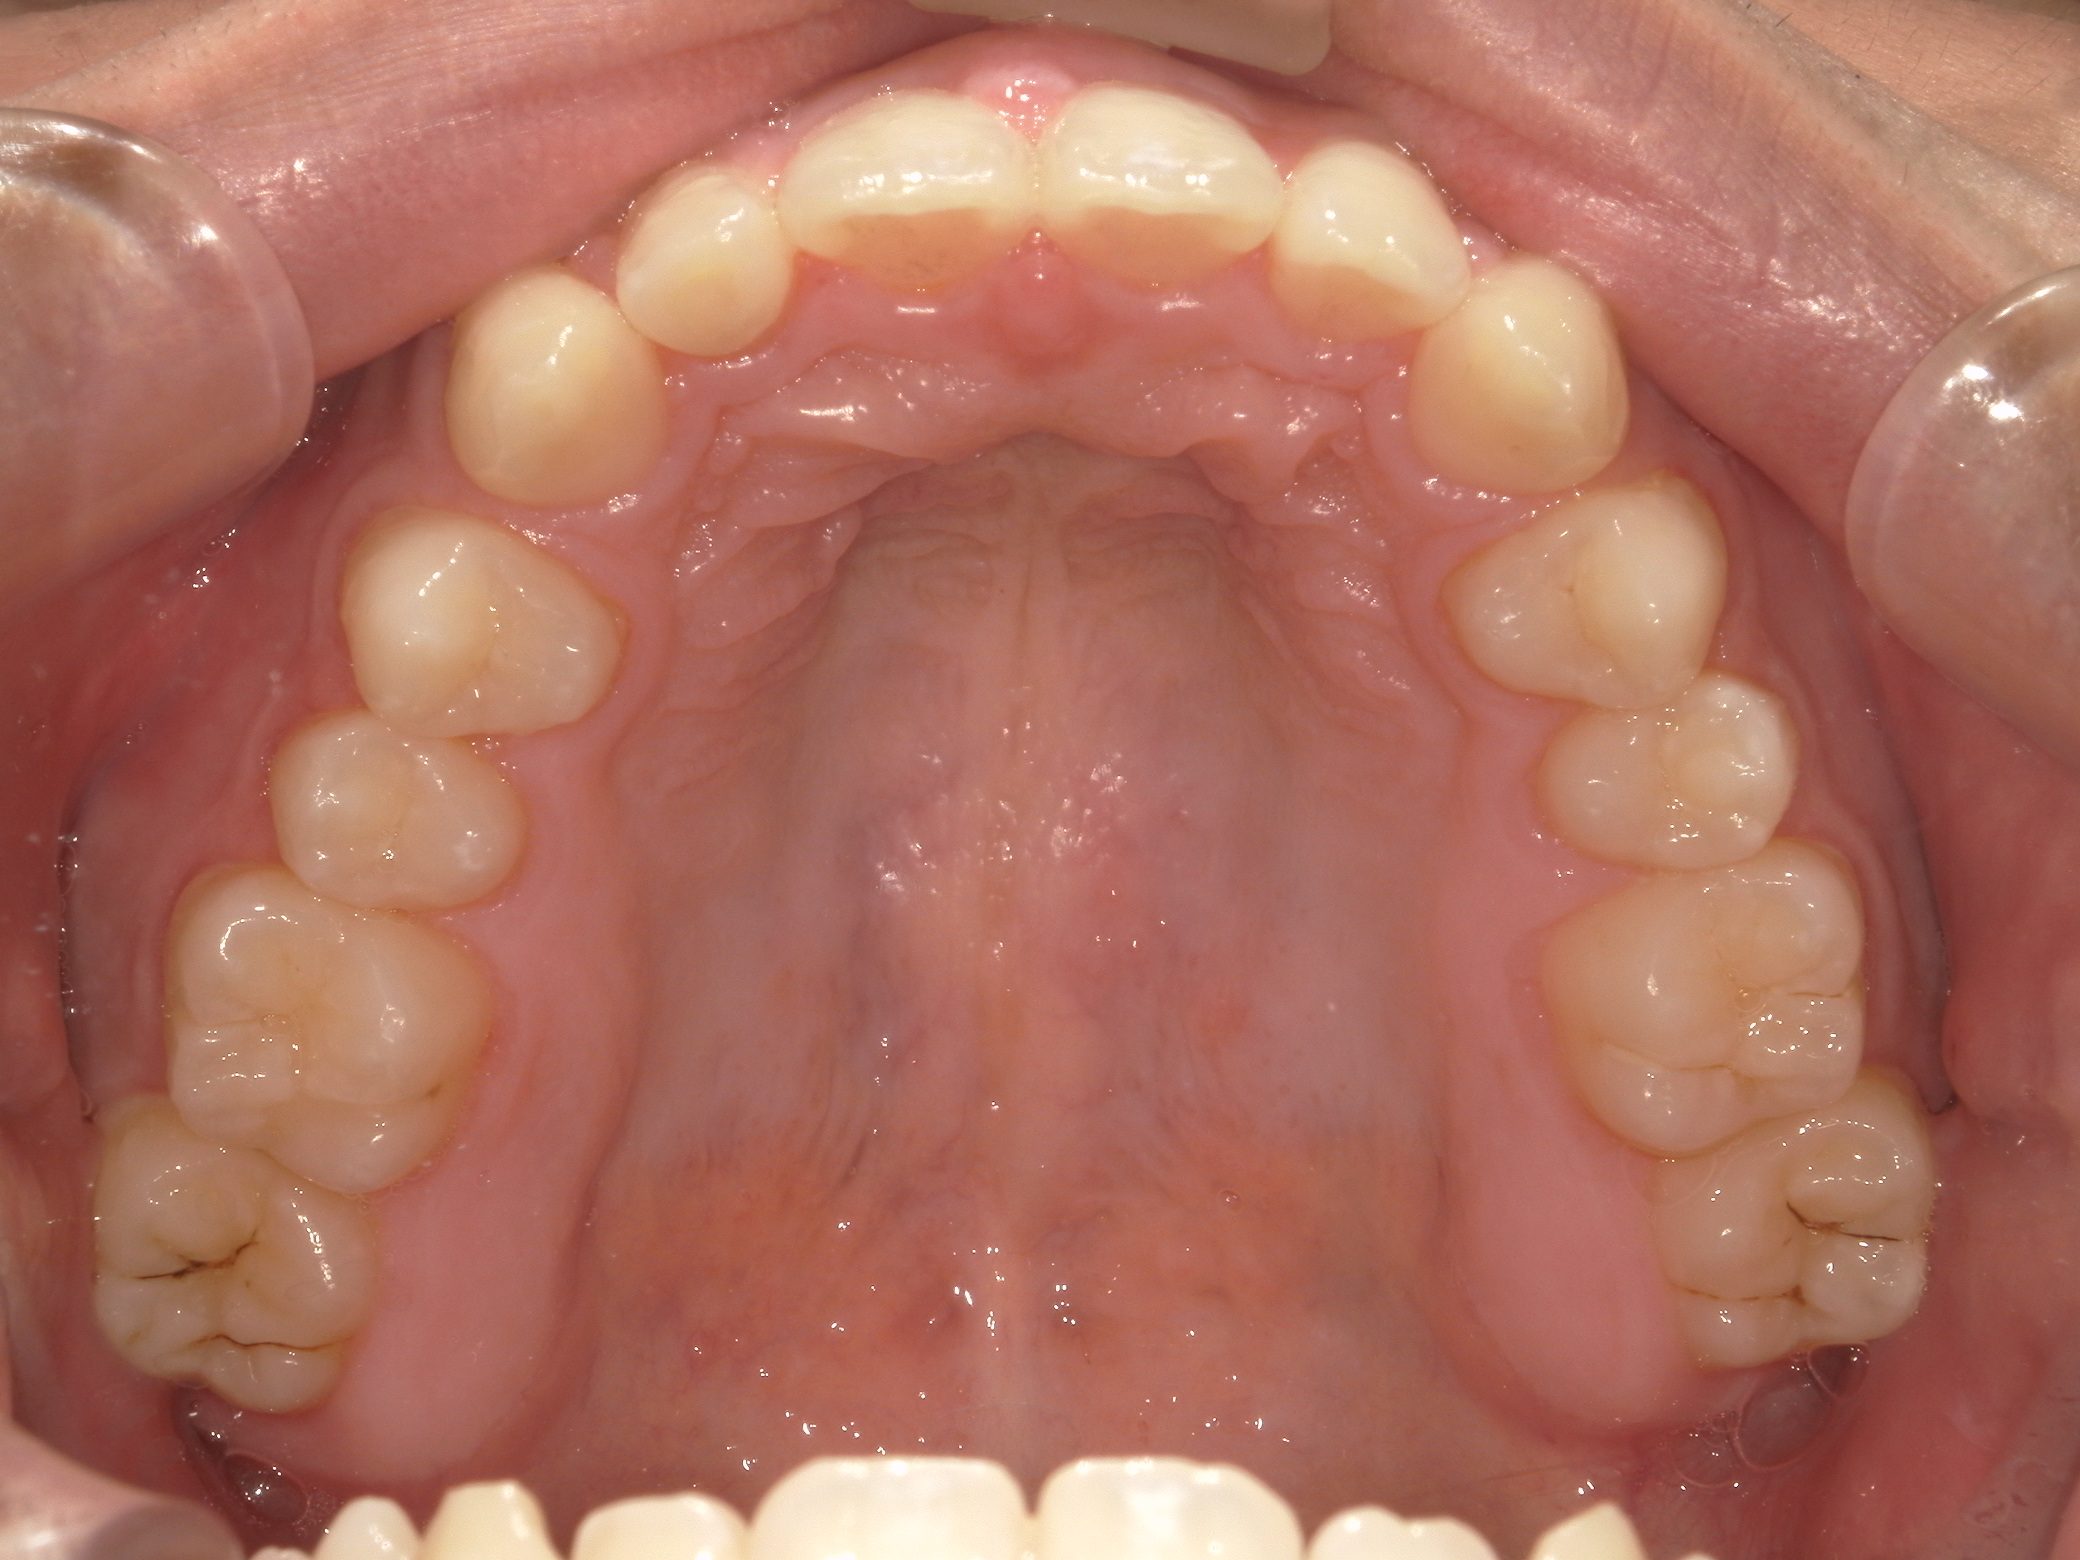

Before

After

治療期間

10か月年

治療開始

19歳

種類

インビザライン矯正

使用装置

インビザラインフル

コメント

すきっ歯なので ディスキングなどもなし

県外の大学に進学されていたので2カ月ごとの来院で10か月で終了

一番奥の歯がすれ違い咬合でしたが、綺麗に治りました。